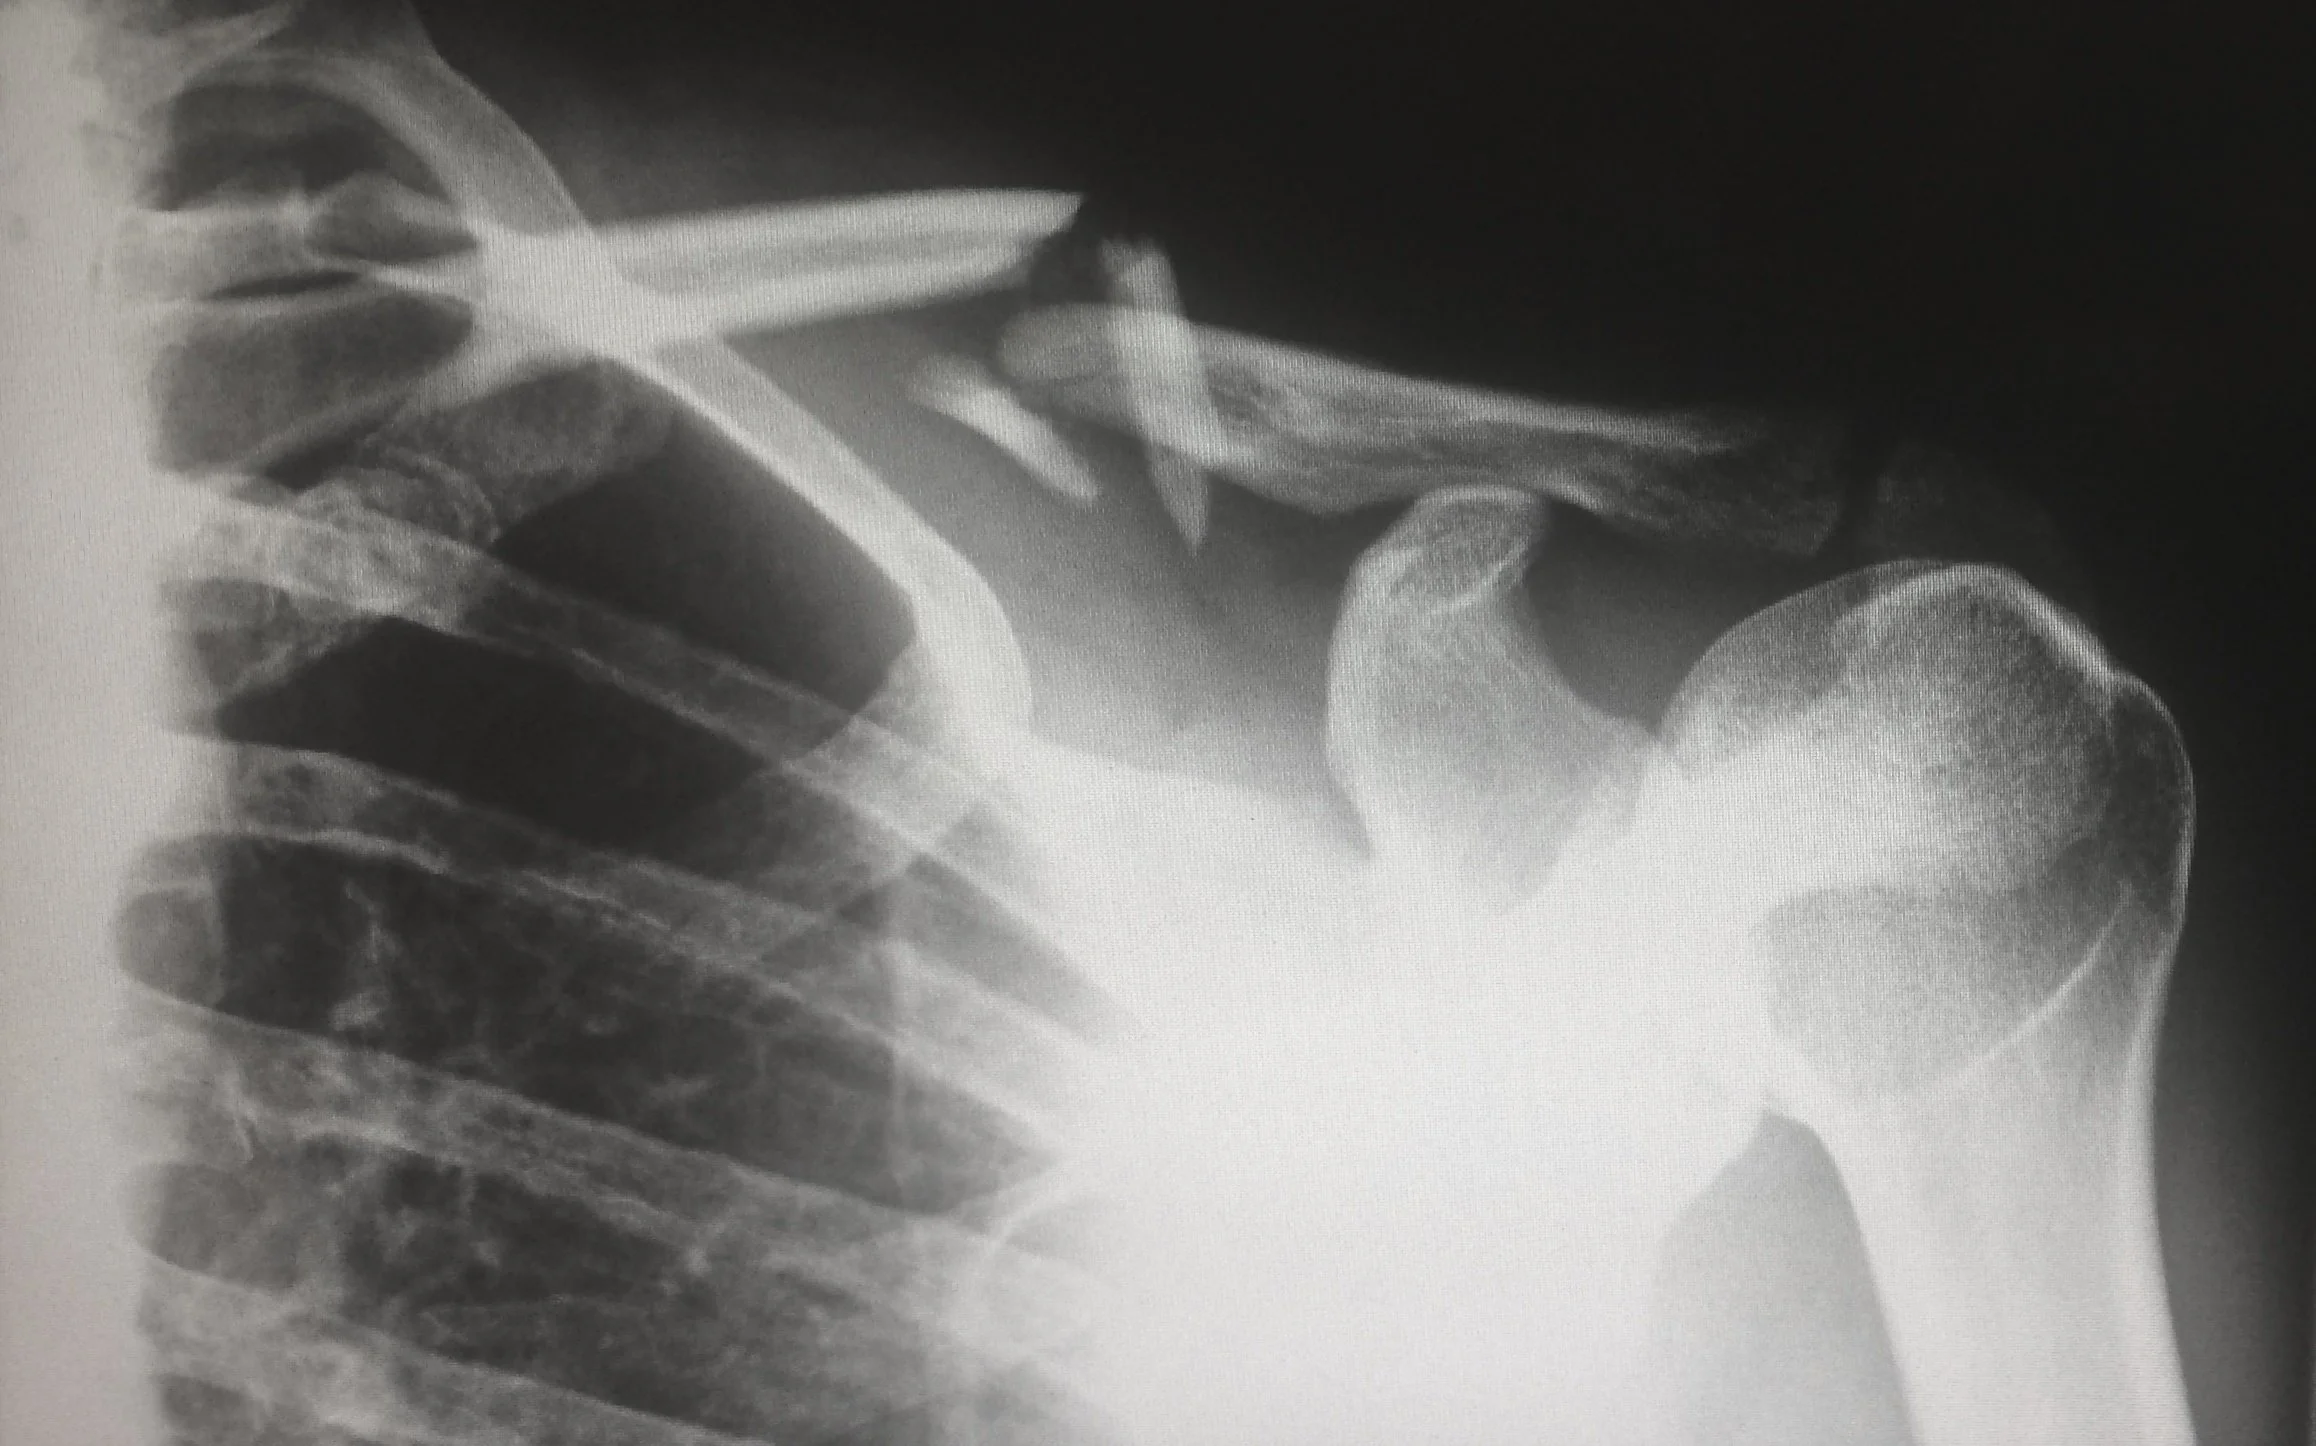

Fractures are diagnosed through imaging such as an X-ray, MRI, CT scan, or a bone scan.

Diagnosing a sprain is typically based on a physical examination and report by the patient.  X-rays may be used to rule out a fracture or dislocation.  X-rays can’t detect pure muscle injuries though.  An MRI can be helpful in determining the location and severity of the injury.

The diagnosis is typically based on a physical examination and report by the patient.  X-rays may be used to rule out a fracture or dislocation.  X-rays can’t detect pure muscle injuries though.  An MRI can be helpful in determining the location and severity of the injury.